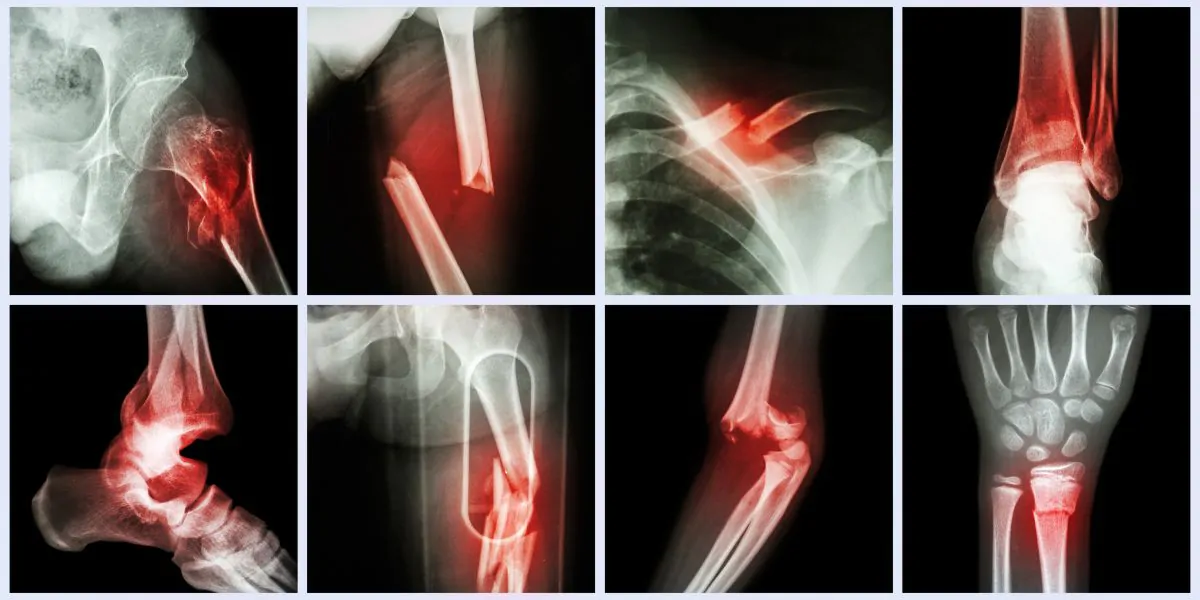

10. إصلاح كسور القدم أو الكاحل

الهدف من جراحة كسر القدم أو الكاحل هو إعادة تنظيم العظام وتثبيتها وإزالة أو إصلاح أي أنسجة رخوة تالفة. قد تثبت البراغي أو الصفائح العظام في مكانها أثناء التئامها. بعد ترميم القدم أو الكاحل المكسور، ستحتاج إلى الراحة ورفع الكاحل لضمان الشفاء السليم على مدار عدة أشهر.